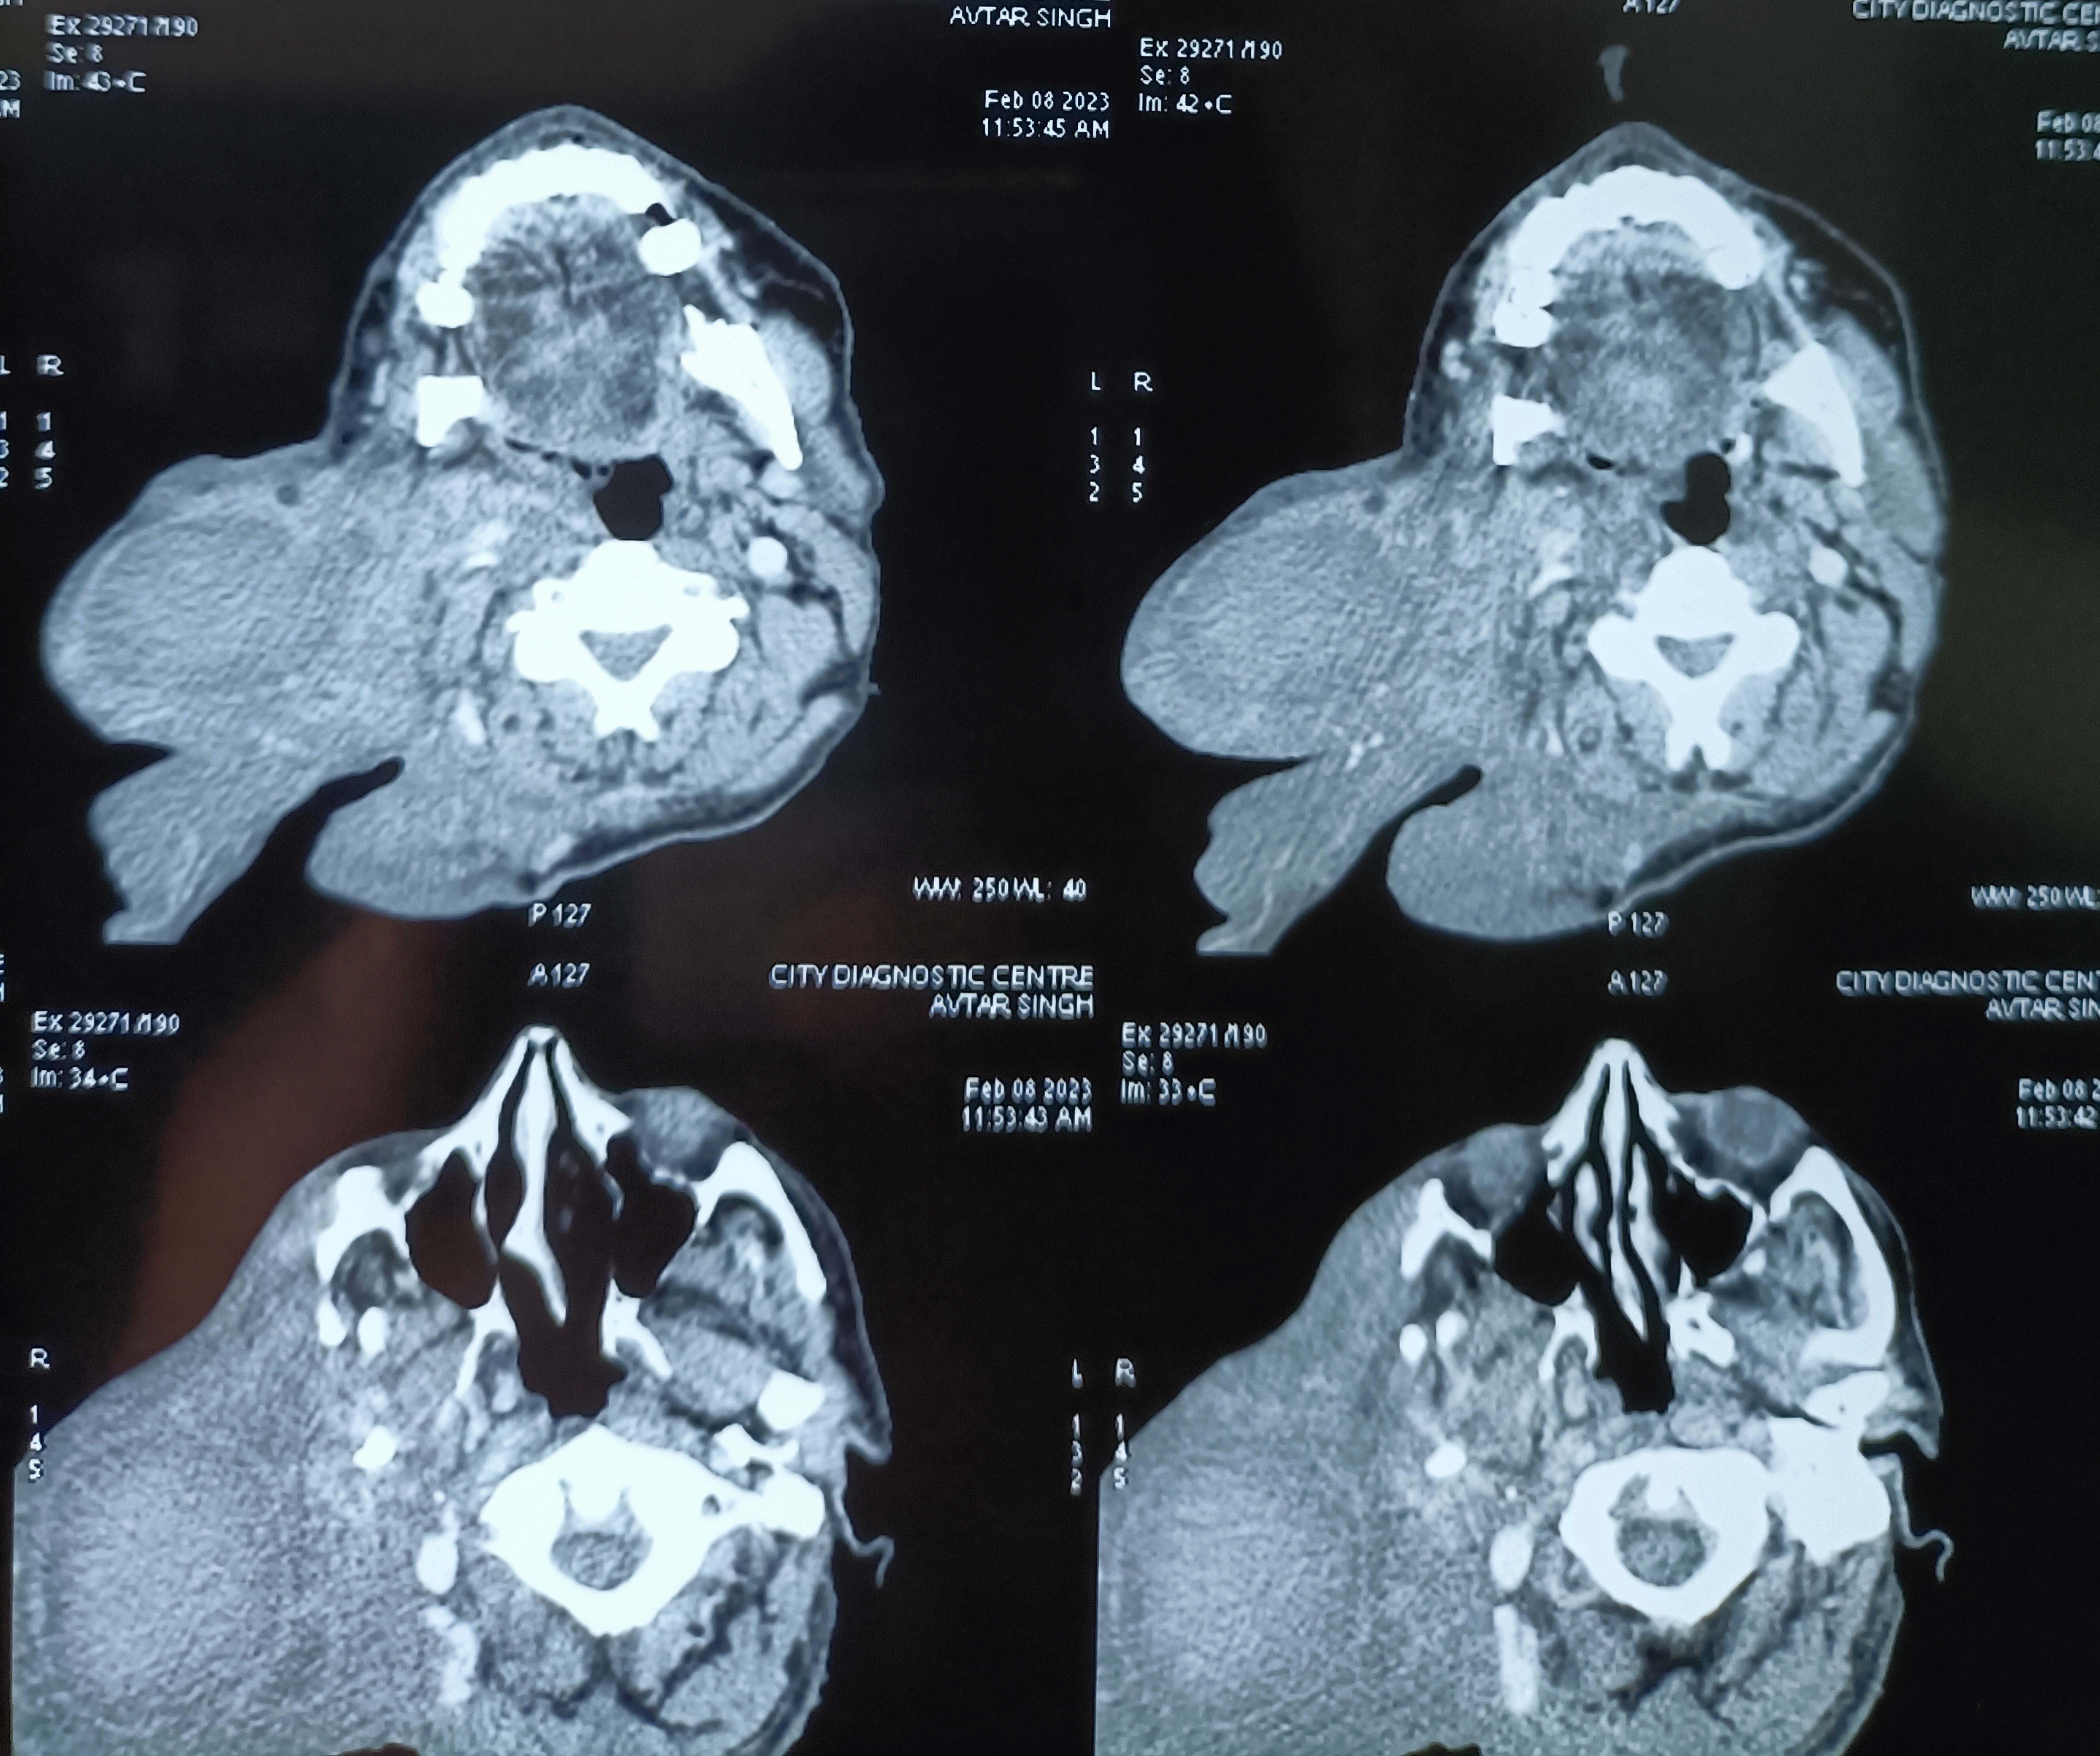

An old man, nearly 70 years of age, presented in OPD with huge plexiform neurofibromatosis of the face and back, with a history going back to more than 50 years. He was now distressed particularly by the big facial lesion and wanted excision.

The facial lesion had brought down his pinna too, and he was unable to hear on that side. An MRI showed much deeper involvement, with destruction of the facial and cranial skeleton, suggesting malignant transformation. Was referred to neurosurgery department PGI.